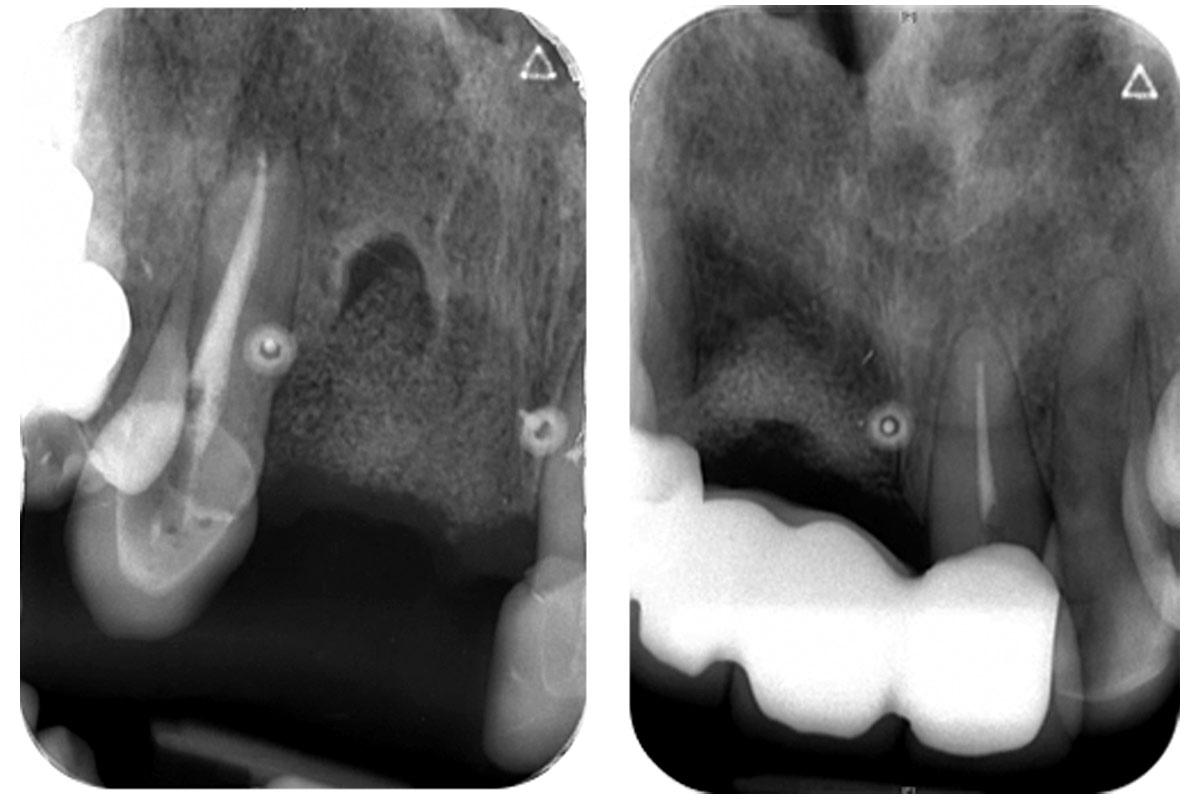

09/10 - Pre-operative x-rayMaxillary bone reconstruction in the anterior area with cerabone® and Jason® membrane - Dr. P.-Y. Gegout & Prof. O. Huck

10/10 - Post-operative x-ray after 22 months; a bridge solution was selected as the adjacent teeth required also crown replacementMaxillary bone reconstruction in the anterior area with cerabone® and Jason® membrane - Dr. P.-Y. Gegout & Prof. O. Huck